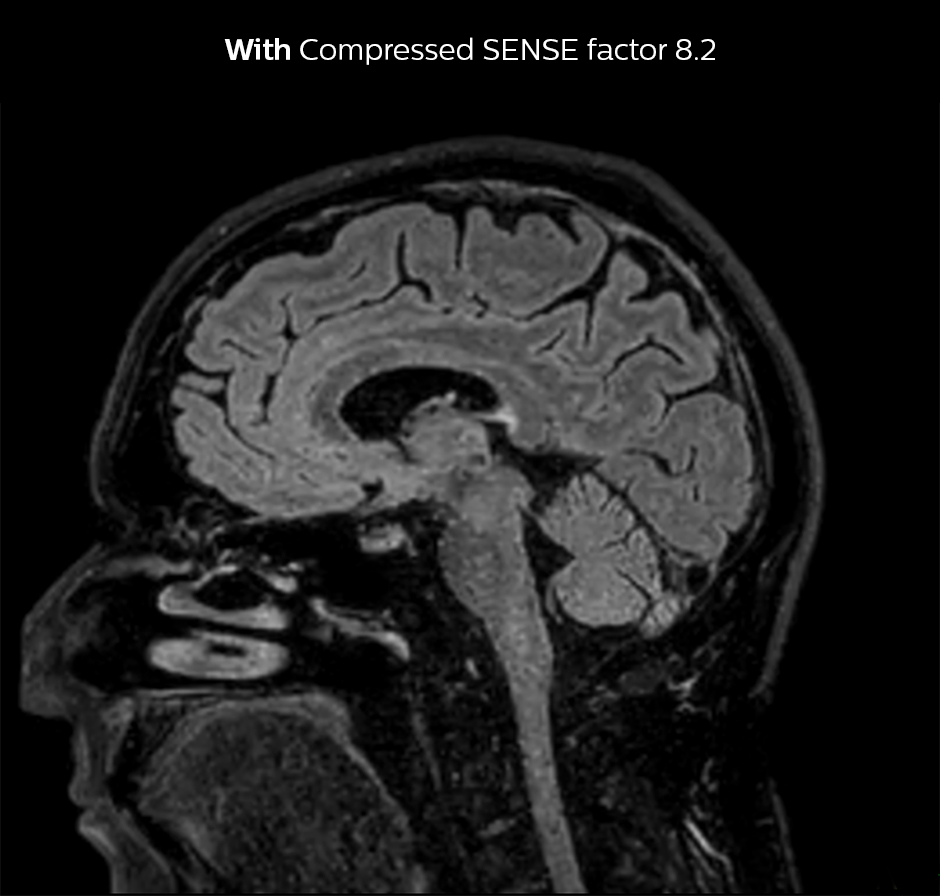

Dr. Sartoretti weet nog goed hoe ze meteen tijdens de eerste scans onder de indruk was van Compressed SENSE. “Onze eerste sequentie met Compressed SENSE was een 3D FLAIR in de hersenen op de Ingenia 1.5T, waarbij we een Compressed SENSE-factor van 8.2 toepasten. Daarna hebben we een 3D TSE mDIXON post-contrastsequentie met een CS-factor van 7 uitgetest. In beide gevallen was de kwaliteit bijzonder goed.“

3D FLAIR, scantijd 5:02 min, voxelgrootte 1,1x1,1x1,1 mm, Ingenia 1.5T.

3D FLAIR, scantijd 3:36 min, voxelgrootte 1,1x1,1x1,1 mm, Ingenia 1.5T.

Compressed SENSE verkort de scantijd met 28%, mét behoud van dezelfde ruimtelijke resolutie.